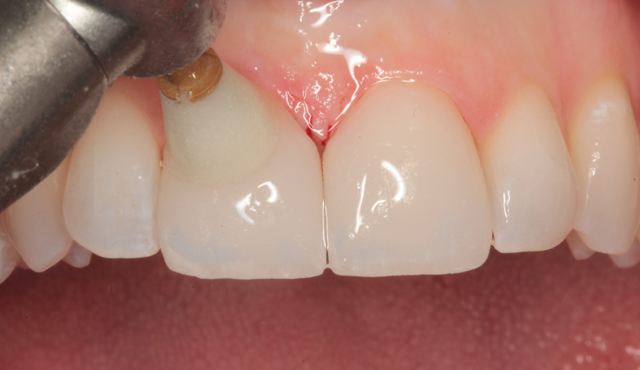

A preoperative impression was taken using Silginat alginate alternative impression material by Kettenbach. The previous laminates were carefully removed using a fine diamond bur (Brasseler) in a high speed handpiece with water spray. The prepared teeth can be seen from the facial view in Figure 4. The incisal view of the prepared teeth is shown in Figure 5. All prepared surfaces were in enamel.

Fig. 4 Fig. 5